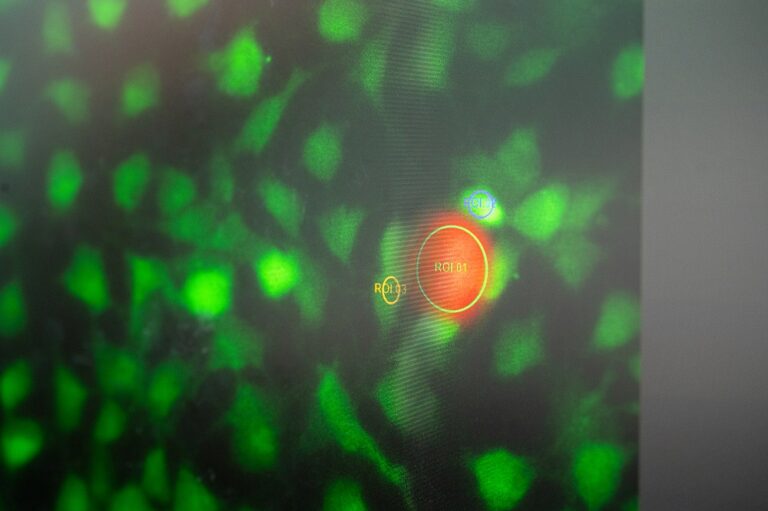

Der Farbstoff Rhodamin-B verleiht dem Mikroroboter seine orange Farbe. Deren Intensität gibt Aufschluss darüber, wie warm er ist.

Foto: Astrid Eckert / TUM

TACSI steht für „Thermally Activated Cell-Signal Imaging“ und bezeichnet ein bildgebendes System, das auf die Erwärmung und Aktivierung von Zellen spezialisiert ist. Interessanterweise klingt die Aussprache des Akronyms wie „Taxi“, was durchaus passend ist: Der Mikroroboter ist darauf ausgelegt, präzise zu den zu untersuchenden Zellen zu navigieren.

- Fluoreszierender Farbstoff: Der Mikroroboter enthält orange Rhodamin-B, einen Farbstoff, dessen Intensität abnimmt, wenn die Temperatur steigt. Dies ermöglicht es dem Mikroroboter, als ein Art Thermometer zu fungieren.

Die Forschungen unter der Leitung von Prof. Berna Özkale Edelmann haben gezeigt, dass die Aktivität von Ionenkanälen in Nierenzellen durch gezielte Temperaturveränderungen beeinflusst werden kann. Dazu näherten sich die Wissenschaftlerinnen und Wissenschaftler den Zellen mit den speziell entwickelten TACSI-Mikrorobotern. „Über den Infrarotlaser haben wir die Temperatur erhöht und über die Intensität von Rhodamin-B die Temperatur bestimmt“, erläutert Wissenschaftler Harder.

Die Ergebnisse zeigten, dass sich die Ionenkanäle der Zellen bei bestimmten Temperaturen öffnen und beispielsweise Kalzium in die Zelle einströmen lassen. „Wir haben an diesem konkreten Beispiel gezeigt, dass Wärme konkrete Änderungen in der Zelle bewirkt, und zwar schon bei leichten Temperaturerhöhungen“, sagt Özkale Edelmann. Sie hofft nun, dass diese Erkenntnisse den Weg für neue therapeutische Ansätze ebnen könnten, etwa durch das gezielte Einschleusen von Wirkstoffen in die Zelle.